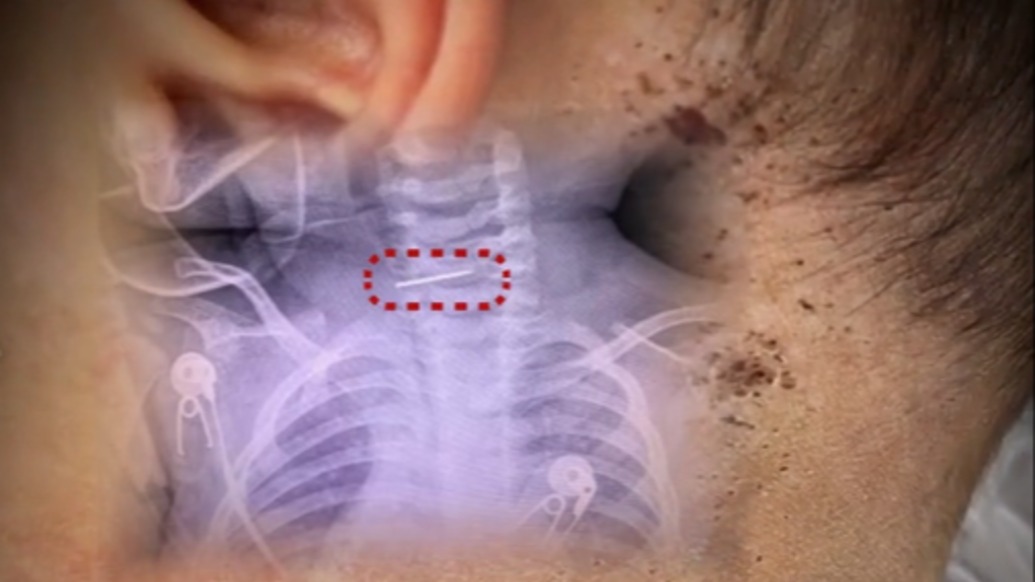

医生接诊发现“男婴颈椎藏针”,警方回应孩子生母精神状况称在开展核查

脊柱外科隋医生发帖称,在昆明接诊一名10个月大的男婴,在其颈椎发现一根针,男婴母亲有些精神异常。云南墨江县公安局和妇联人员表示,正在做相关工作核查,男婴在医院治疗,其母亲也已送医。